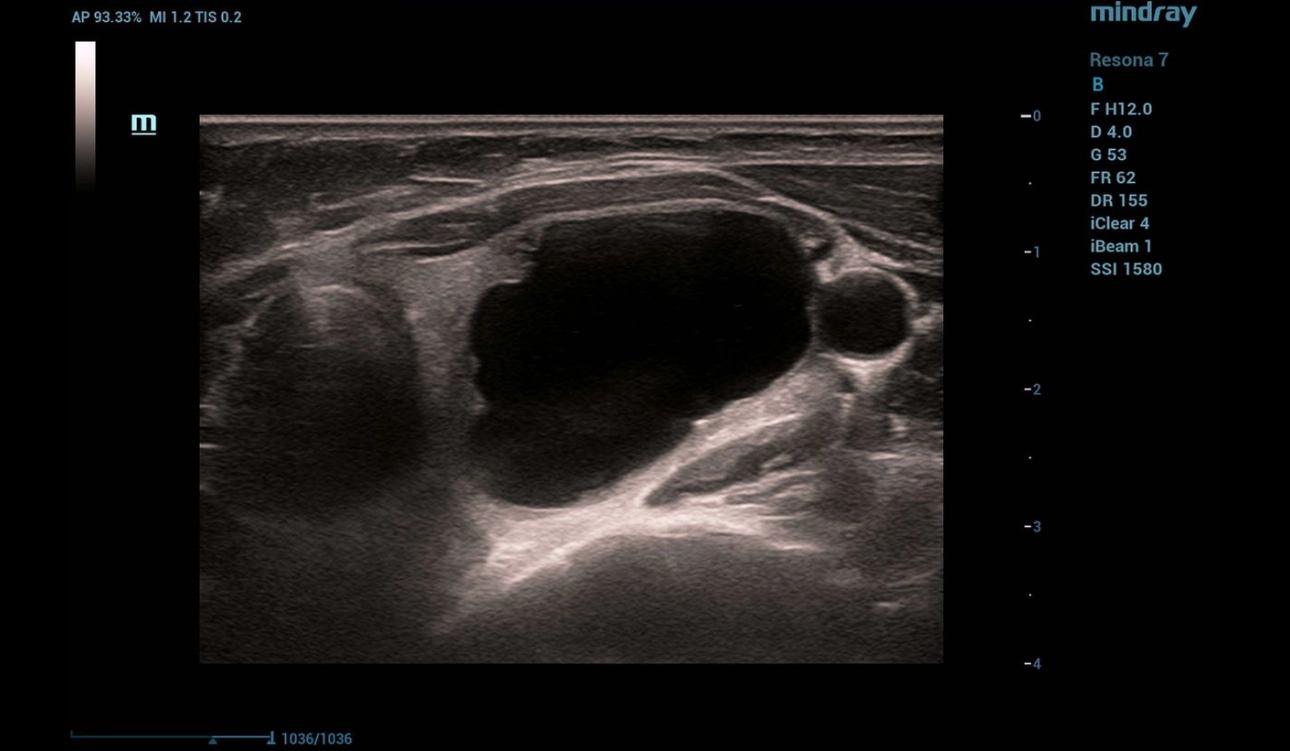

B-mode and Color Flow Doppler (CFD)

Ultrasonography was performed on a Resona 7 ultrasound machine (Mindray, China) using a linear probe L14-5WU. A cystic focal mass of anechogenic structure measuring 24x28x38 mm with smooth clear contours was detected in the left lobe of the thyroid gland (Fig. 1, 2)

Figure 1. B-mode image of the thyroid